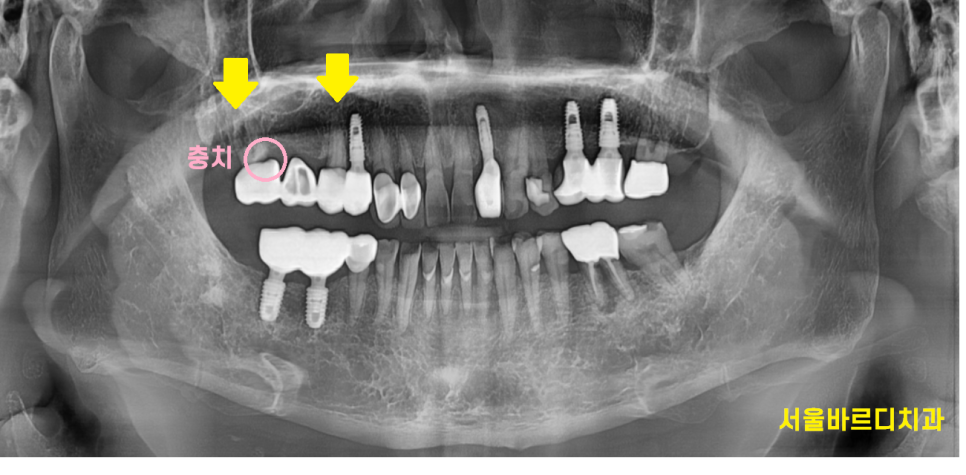

고덕동 치과치료를 위해 방문해주신 환자분

치료한지 20년 가까이 된 치아라 하셨습니다.

언제 치료했는지 기억도 못하지만

흔들리고

냄새도 나는 것 같아서

이가 상했다며

방문해주셨습니다.

이제는 취급을 잘 안하는

은니를 사용해 씌운 치아입니다.

세월의 흔적을 보여주는 증거네요~

치아에 충치도 있고

잇몸 뼈도 녹아 흔들리고

예후를 생각하여 씌운 치아 뽑아서

고덕동 임플란트로 교체하는 것으로

상담해드렸습니다.

23.05.15

3d-ct를 통해

남아있는 뼈 분석하고 임플란트까지 완료했습니다.